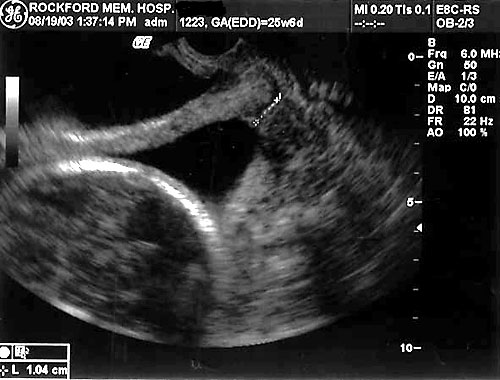

Normal fetal bladder at 18 weeks (left, at arrow). Lovely picture of both uterine arteries around normal bladder (right). This color flow picture documents the presence of the 3 vessel cord with the demonstration of the two uterine arteries coursing around the bladder. - Spine (need two perpendicular views)